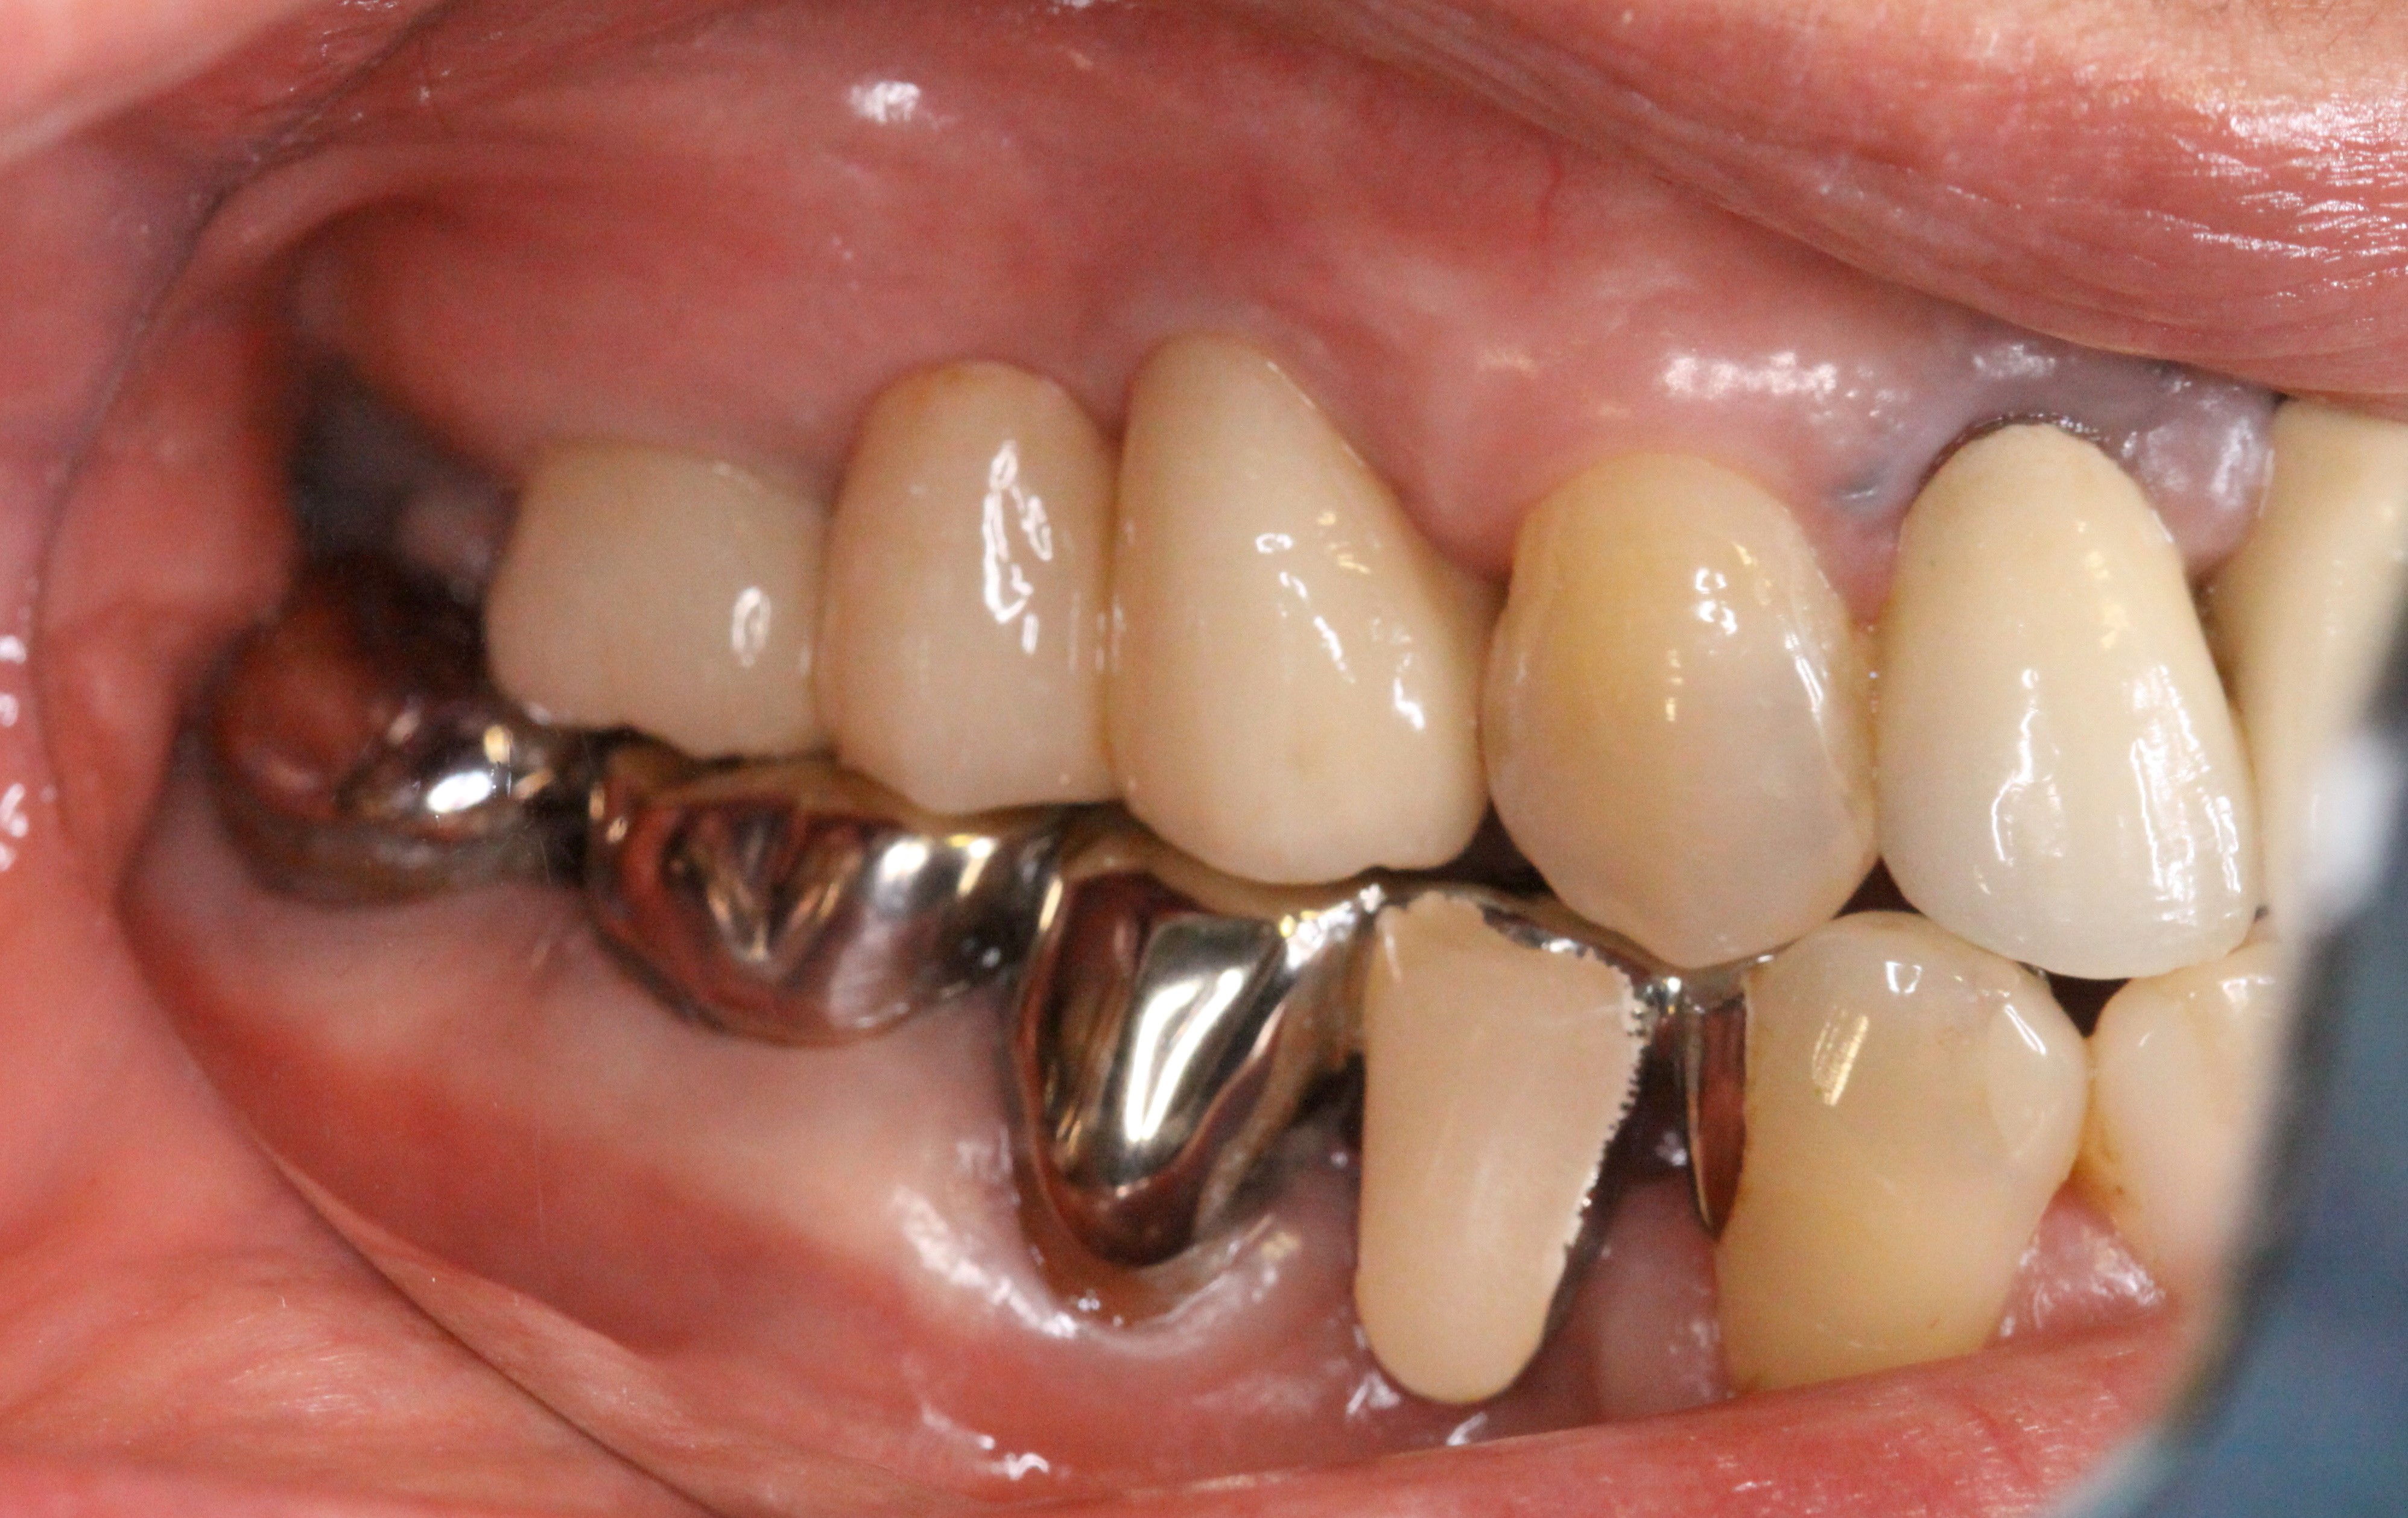

再植後

治療前

補綴後

治療途中

再植後、4~6か月程経過を見て骨や歯茎の状態が良くなってきたところで被せ物を入れていきます。